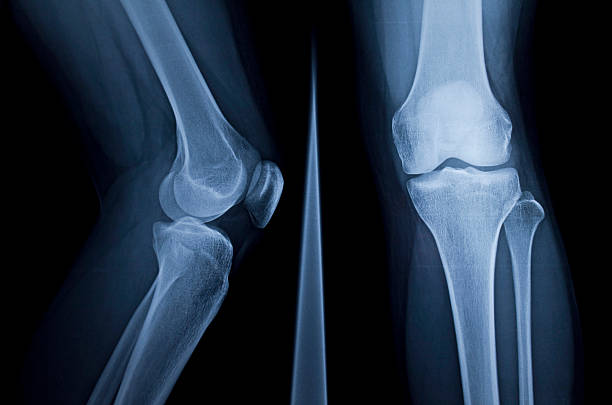

무릎 관절염에 의한 무릎 통증

무릎 관절염은 무릎 관절의 연골과 주변 조직들이 염증을 일으키는 질환으로, 노화, 과부하, 외상 등이 원인이 됩니다. 무릎 관절이 불안정해지고 염증이 발생하면 통증, 부종, 관절 강직 등의 증상이 나타납니다. 운동, 체중 감량, 약물 치료 등이 치료 방법으로 사용됩니다. 특히 중증도가 높은 경우 수술 치료가 필요할 수 있습니다.